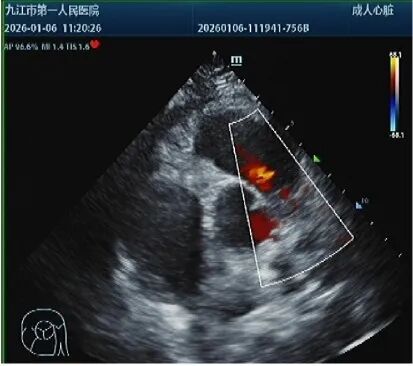

经床边超声、心电图等检查,医生快速确诊:患者急性右心扩大、肺动脉高压,双下肢静脉有血栓,且左股静脉有血栓游动,另有典型的SⅠQⅢTⅢ心电图改变,结合患者低血压,诊断为高危急性肺动脉栓塞。进一步肺动脉PTCA检查显示患者双肺多处肺动脉分支被血栓阻塞,死亡风险极高。